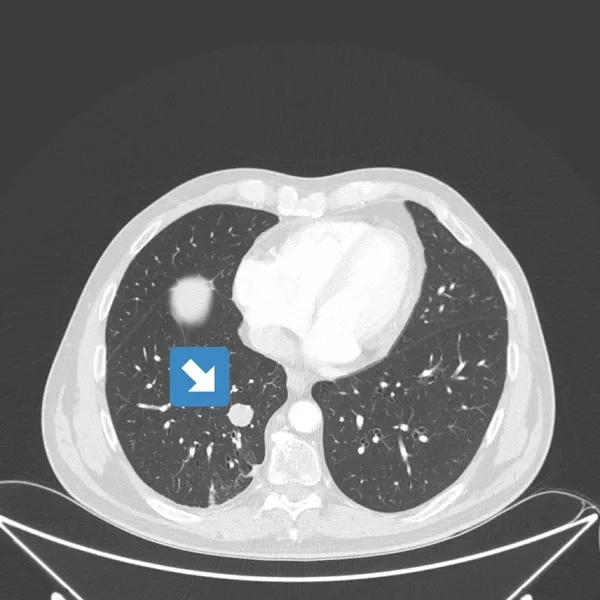

Prof. Dr. Güner Sönmez, "Evre 4 akciğer kanseri hastanın Covid 19 öncesi ve sonra çekilen akciğer tomografisi.

Akciğerdeki metastaz kaybolmuş. Daha önce de bir lenfoma hastasını paylaşmıştım; Covid sonrası tamamen lenfoma bulguları kaybolmuştu.

Muhtemelen Corona virüse karşı oluşan antikorlar ve hücresel bağışıklık, kanser hücrelerine de müdahale ediyor." ifadelerini kullandı.